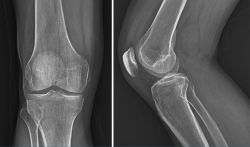

3. Artrosis

La gonartrosis es la causa más frecuente del dolor de rodilla después de los 50 años. En la radiografía se observa una reducción de la interlínea femorotibial o femoropatelar, y una osteofitosis marginal (Figura 6).

Figura 6. Radiografías anteroposterior y lateral de rodilla: osteofitos en compartimentos femorotibial y femoropatelar.